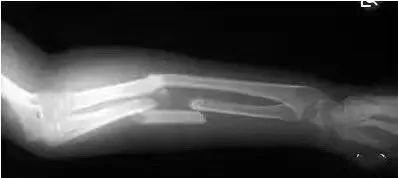

(10)尺骨上1/3骨折合并桡骨头脱位尺桡骨干双骨折:症状、体征相似,儿童及成人均可见;X线片示无桡骨头脱位征。

(11)尺桡骨干双骨折孟氏骨折:在肘前方可触及脱位的桡骨头关节面,X线摄片可见桡尺骨干双骨折,尺骨骨折线在近1/3处并有桡骨头向前脱位。

(12)桡骨下1/3骨折合并下尺桡关节脱位

尺桡骨干下1/3骨折:前臂中下段肿痛、畸形,异常活动,前臂旋转功能受限,尺桡骨下1/3可扪及骨擦感,前臀活动障碍更明显;X线片示尺桡骨干下1/3骨折,无下尺桡关节脱位。

桡骨下段骨折并下尺桡关节脱位:腕部肿痛、增宽,腕关节屈伸活动受限,明显餐叉样畸形,无桡骨下1/3处异常活动;X线片常见合并尺骨茎突撕脱。